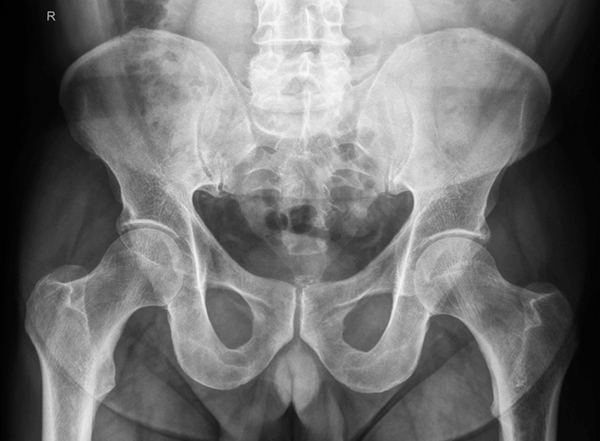

- Röntgenaufnahmen (CT/MRT optional): Um das Ausmaß der Gelenkschäden zu beurteilen.

Röntgenbild Beckenübersicht mit beiden Hüftgelenken